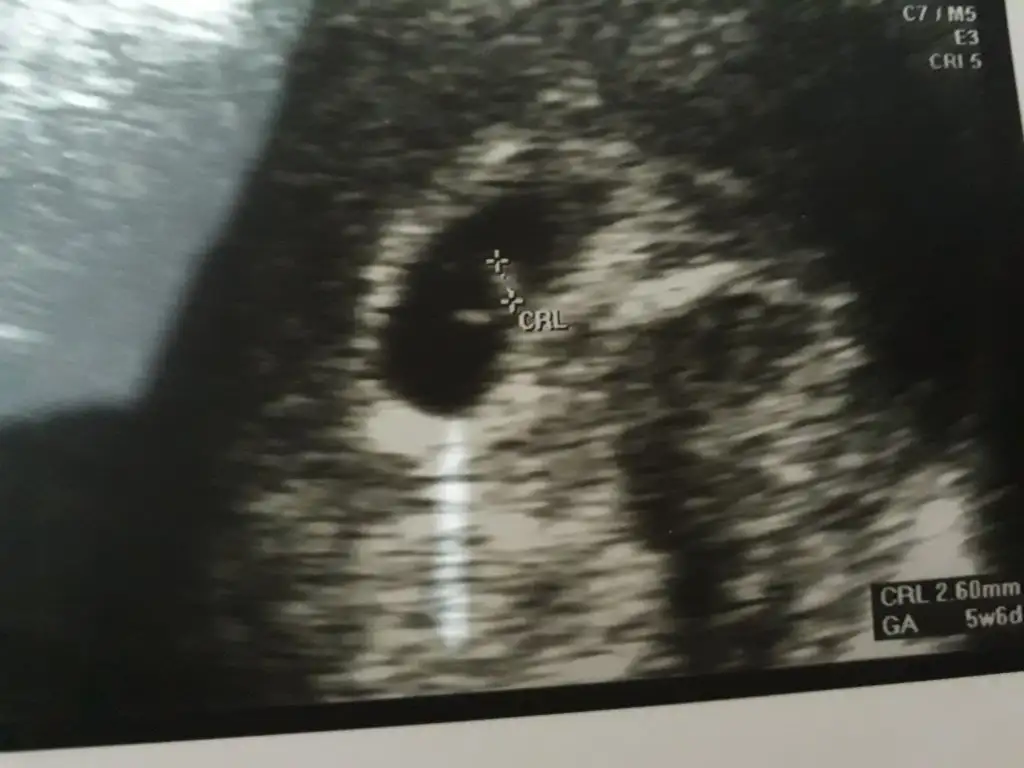

Canım panik yapma ben 6 da gördüm hepsini. Hatta karından baktılar bende kese bile yoktu. Doktor dış gebelikten şüphelendi. Vajinal bakmak gerek dedi ben de korkuyorum dedim hatta beni sakinleştirdi bakmamız gerek dedi. Bakınca bebek de oradaydı kese de. Ama karından hiç görünmedi. Hatta bak vajinal resmni ekliyorum 6 haftalık resmi

Eklentiler

• IMG_20191011_175501~2.webp

IMG_20191011_175501~2.webp

21,2 KB · Görüntüleme: 65